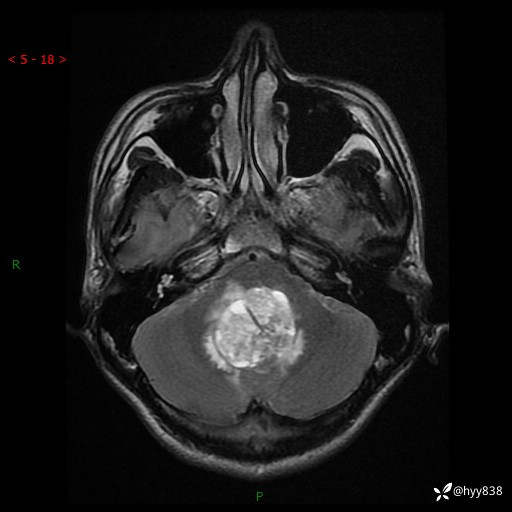

性别:男

年龄:17岁

简要病史:头痛伴间断性呕吐1月余,外院CT提示颅脑占位

颅脑MRI平扫+增强